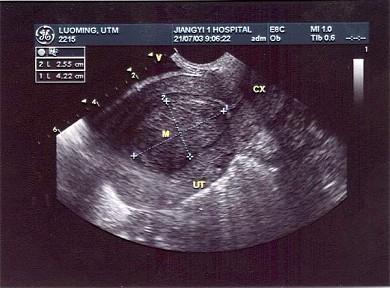

某患者月经量多就诊,经阴道超声声像图如下,最可能的超声诊断为?(?)A.子宫内膜癌B.子宫粘膜下肌瘤C.绒癌D.子宫腺肌症E.子宫浆膜下肌瘤

问题 某患者月经量多就诊,经阴道超声声像图如下,最可能的超声诊断为?(?)

选项 A.子宫内膜癌 B.子宫粘膜下肌瘤 C.绒癌 D.子宫腺肌症 E.子宫浆膜下肌瘤

答案 B